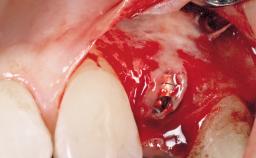

Late Flapless Placement of an Implant in a Maxillary Left Central Incisor Site

Bone Augmentation Horizontal|Staged

Augmentation Materials Xenogenous|Membrane

Soft Tissue Grafting Simultaneous

Bone Volume Deficient horizontally, requiring prior grafting